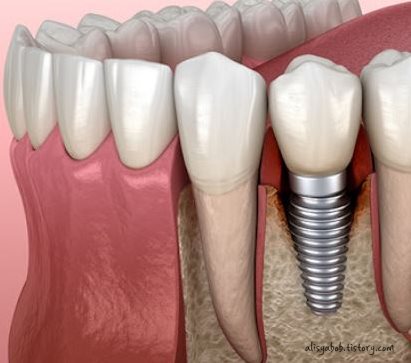

임플란트는 치아가 빠진 부위에 치워 버리리 역할을 하는 인공 치근을 고정하고 그 위에 지대 주를 연결한 이후에 보철물을 올려 마치 자연치아 위 기술을 하는 인공 치아 시립 치료 형태를 말합니다. 임플란트 치료 과정은 진단 1차/2차 수술 보철물 장착 수술 후 관리 등을 거치게 되는데요,